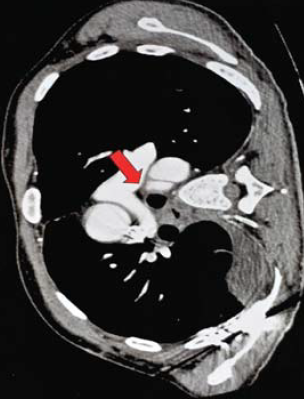

6. ábra.

7. sorszámú betegünk CTA vizsgálata multiplex gerinc, borda és jobb oldali acetabulum törés mellett kialkult isthmicus aorta intima sérülését mutatja.

7. 32 éves férfi autóbaleset okozta koponyaűri és arcüregi vérzéssel, agyödémával, kétoldali pleuralis és mediastinalis folyadékgyülemmel, PTX és hasi szabad levegővel, máj és lép körüli kevés véres folyadékkal, felső thoracalis és lumbalis csigolya és jobb lapockatöréssel, jo. acetabulum töréssel, femur luxatioval, kiterjedt mellkas és hasfali subcutan emphysemával, intubálva eszméletlen állapotban került felvételre. Neurologiai statusának rendeződése, mellkasi sérüléseinek ellátása és fracturáinak műtéti rögzítése után, 16 nappal a sérülés követően, a. subclavia transpositiot elvégezve, isthmicus stentgraft beültetés történt. A bal lapockatörés után kialakult dorsalis septicus haematomája 2 hónapos kezelés után gyógyult (6.,7.,8. ábra).